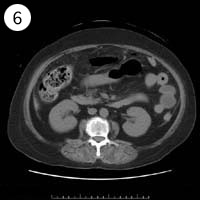

57歳 女性

単純CT

造影CT

※異常画像を赤枠で示しています